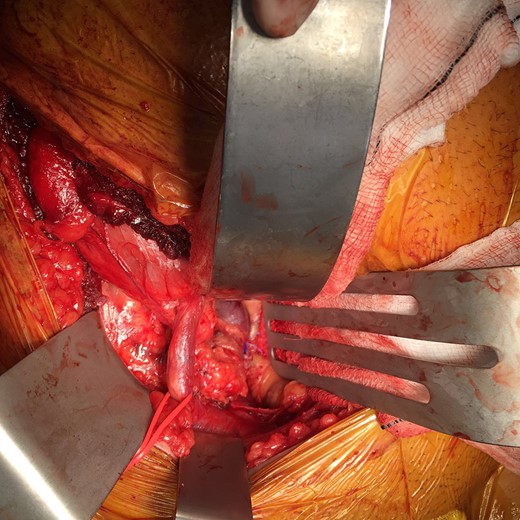

A 26-year-old man was referred to our vascular surgery tertiary referral service from his local hospital with leg size discrepancy (right > left) and prominent right leg varicose veins distally. He had lower urinary tract symptoms (frequency >30 times per day) for a year prior to presentation but had no leg symptoms in relation to his varicosities. His past medical history was of premature birth, as one of triplets, who spent a prolonged period on a neonatal intensive care unit. The patient thought he may have had a deep vein thrombosis in his right leg as a child. An MRI of his right thigh and pelvis demonstrated a 5 cm venous aneurysm (EIV), indenting the bladder, and generalized distal venous dilatation of both deep and superficial veins. He subsequently underwent venography, which confirmed an aneurysmal EIV, with massive collateral dilatation of trans-pelvic veins and complete occlusion of the right common femoral vein (CFV). A concurrent attempt at endovenous stenting was made, but was unsuccessful as the CFV could not be passed with a guide-wire and no alternate route was found possible. Further characterization by CT demonstrated a dilated and tortuous right internal iliac vein (IIV) feeding the aneurysm (Fig. 1). A multidisciplinary decision was made to proceed to operative repair, in light of the patient’s debilitating urinary frequency from the mass effect of the aneurysm. Pre-intervention venous severity scoring was not pursued as the patient’s symptoms were only bladder-related. The patient underwent an open aneurysmectomy via a Rutherford-Morrison incision, with concurrent right retrograde ureteric stent placement. Intra-operatively, a wide-necked aneurysm was confirmed to arise from the EIV (Fig. 2) in a saccular fashion. The aneurysm was clamped at the neck and closed with 3-0 Prolene (Ethicon, Inc., New Jersey, USA) leaving a normal calibre EIV (Figs 3 and 4). The IIV remained patent at the end of the procedure and a venous bypass was not performed. The patient recovered well post-operatively and was discharged home four days later, with removal of the ureteric stent prior to discharge. He has been followed up 6-monthly since and remains well at 2 years’ post-operatively. CT venogram has shown a good post-operative result, with no residual aneurysm (Fig. 5). The patient’s pre-operative lower urinary tract symptoms have improved. He did not develop any leg symptoms.

Intra-operative appearance of the external iliac vein aneurysm. A retroperitoneal approach was used via a Rutherford-Morrison incision. Laterally, the external iliac artery is controlled with a vessel loop.